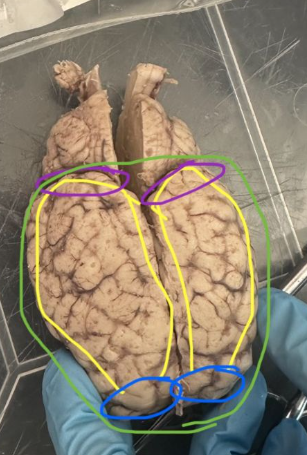

<p>What is the green circle indicating on the sheep's brain?</p>

Olfactory bulb

<p>What is the yellow circle indicating on the sheep's brain?</p>

Optic nerve/chiasma

<p>What is the purple circle indicating on the sheep's brain?</p>

Pons

<p>What is the blue circle indicating on the sheep's brain?</p>

Medulla

New cards

Midbrain

Hypothalamus

Cerebrum

Frontal lobes

Occipital Lobes

Parietal lobes

Cerebellum

<p>What is the color purple indicating on the sheep's brain?</p>

Arbor vitae

<p>What is the red circle indicating on the sheep's brain?</p>

Pineal body/gland

Corpus callosum

Thalamus

Lateral ventricle

Transverse fissure

Superior colliculus

<p>What is the green circle indicating on the human brain?</p>

Brain stem

<p>What is the yellow circle indicating on the human brain?</p>

Medulla oblongata

<p>What is the purple circle indicating on the human brain?</p>

<p>What is the red circle indicating on the human brain?</p>

Cerebellar hemispheres

Vermis

<p>What is the blue circle indicating on the human brain?</p>

Folia

<p>What is the color purple indicating on the human brain?</p>

<p>What are green circles indicating on the human brain?</p>

Cerebellar cortex